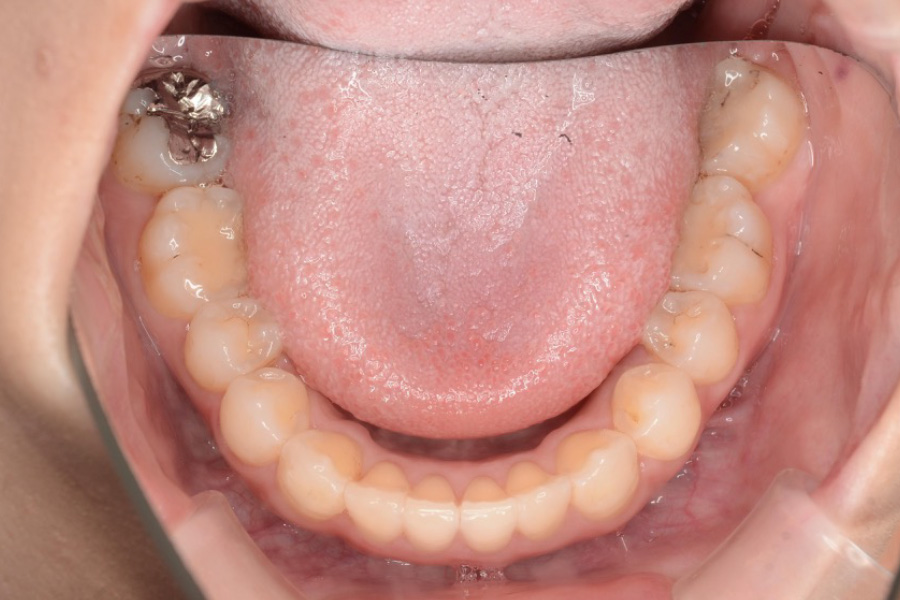

治療後

主訴 歯のガタつき

期間 2年半

治療内容 インビザライン矯正

非抜歯